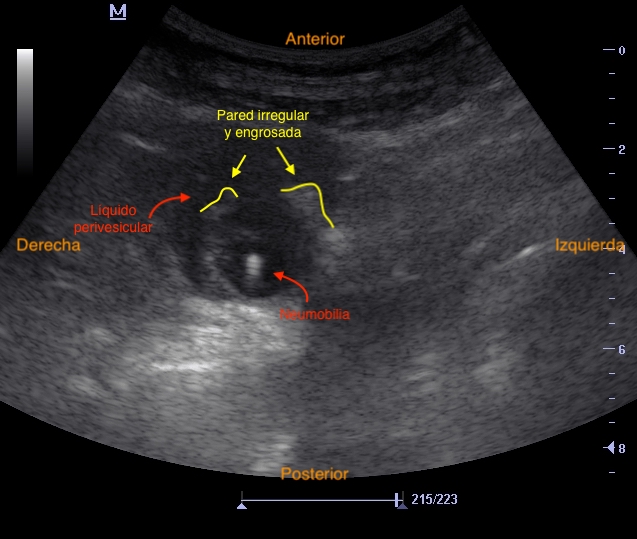

Se visualiza vesícula biliar con contenido hiperecogénico en su interior sugestivo de cálculos biliares, pared anterior engrosada (0,35 mm), con líquido perivesicular y fenómeno de ring-down en su interior (posible neumobilia). Colédoco distal dilatado, con signo del doble cañón, sin clara dilatación de conductos biliares intrahepáticos.

Colecistitis aguda enfisematosa VS colecistitis subaguda.